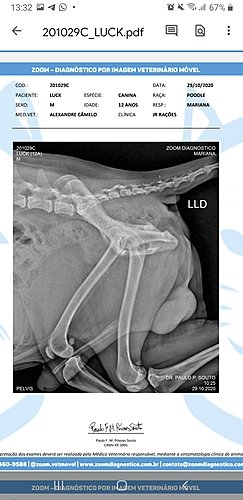

Luck é meu cachorro a 12 anos, até dia 27/10 ele tava andando normal, fomos passear de manhã, mas de tarde ele perdeu a força nas patinhas traseiras, levei ele no veterinário Alexandre dia 28/10 e ele passou 2 medicamentos prediderme 20mg (38,80)e cronidor 12mg 2x ao dia por 20 dias que dá 2 caixas com 10 comprimidos (2x 59.90) e um raio x (200,00), todos esses já comprei e ainda preciso pagar + consulta (70,00). Fora isso, depois que saiu o resultado do raio x alexandre passou o tratamento pra 2 meses com o remédio Gerioox 2 Comprimidos por dia, que dá 4 caixas de 30 comprimidos pra os 2 meses, as 4 caixas são (425,12) + 75,00 (Seniox) + 71,90 (Milgama- esse será pra o resto da vida). A conta total disso fica em 1.001, 00. Dinheiro que foge muito do meu orçamento, me encontro totalmente seNm saber o que fazer e pedindo a vocês qualquer contribuição. É muito doloroso ver ele da forma que está pois ele sente muita dor, não anda devido a isso e tem dificuldade pra defecar porque é uma região proxima que ao fazer força pra defecar doi as articulacoes também e tudo isso tem como melhorar se eu conseguir seguir o tratamento. Preciso muito da ajuda de vocês, eu nem sei como agradecer, quem não puder doar, compartilha, vai ajudar muito. Eu quero muito que meu bichinho fique bem, o Veterinário disse que ele pode voltar a andar e não sentir dor. Muita gratidão a quem ajudar seja de que forma for. Muita gratidão, mesmo.

*** Vou anexar fotos do diagnóstico, dos preços de remédios e etc.